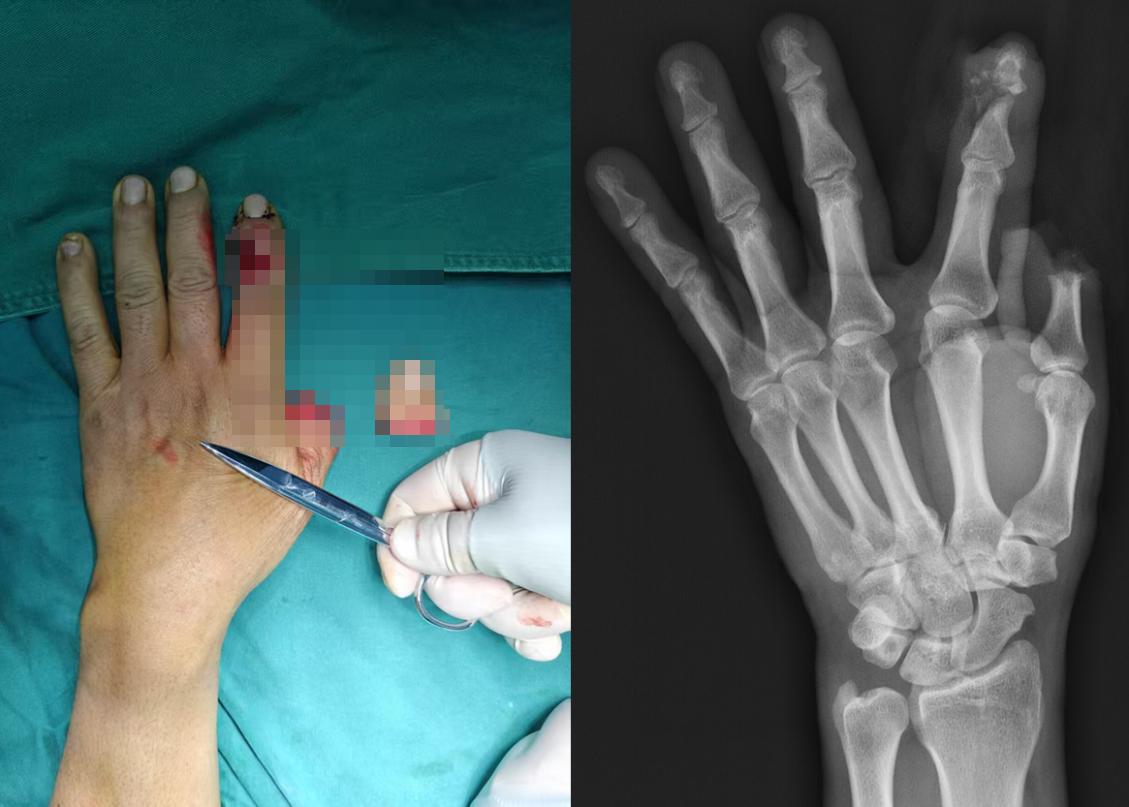

术后苏大附四院医疗团队为患者制定“四防一促”管理方案:防血管危象、防感染、防血栓、防关节僵直、促神经再生。通过毛细血管反流监测、定制化抗凝方案及早期康复介入,患者再植指体顺利度过72小时血管危象高发期。目前,患者拇指及食指末梢血运良好,创口已愈合,提示再植的拇指及食指皮瓣存活。

患者术后左手形态基本恢复,拇指末梢血运良好,术后2周断指基本存活,复查X光片显示拇指及食指远节指间关节对合良好、形态基本恢复正常。